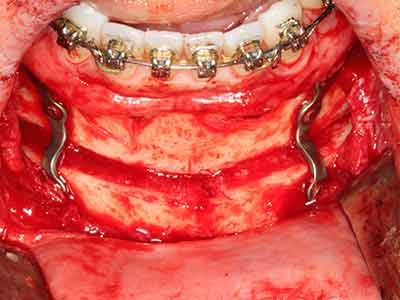

Пиезохирургията има допълнителни предимства при събиране на костни блокове. В допълнение към високата прецизност при остеотомията, описана по-горе, употребата на фините режещи накрайници значително намаляват загубата на материал. Голяма загуба на материал по време на събиране може да се очаква с дебелите накрайници, особено при употреба на борери Линдеман (Lakshmiganthan, Gokulanathan et al. 2012). Базалното разделяне, което е необходимо, особено за присадка на блок при ретромолар, е улеснено от специално създадени правоъгълни триони. В резултат на това, пиезохирургията е разглеждана като прецизна, улеснена и безопасна процедура за събиране на костни блокове в ретромоларното пространство (Happe 2007) (Фиг. 1-12).